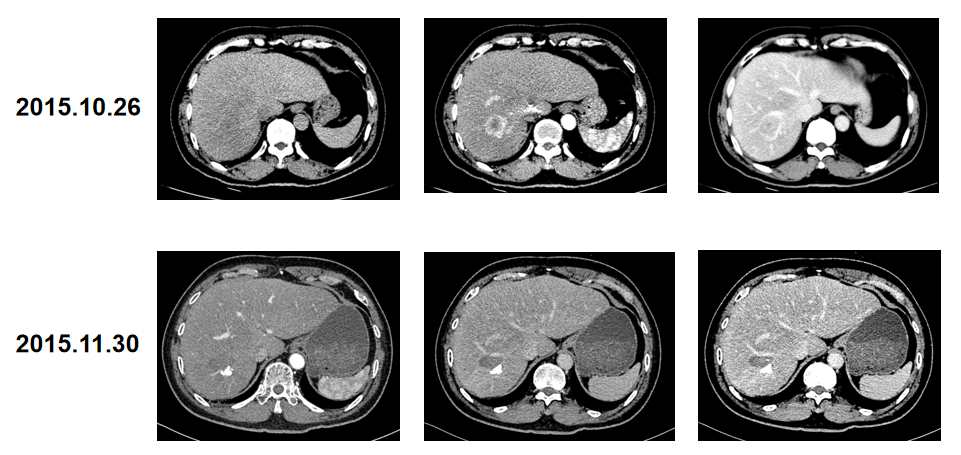

患者自第2周期起,每两个周期(8 W)进行影像学评价,均评价为PR。

2020年1月15日,患者因出现尿蛋白升高、肾病综合征,停药退出研究组,直至退出研究组仍评价为PR(图1)。

Child-Pugh A级肝细胞癌切除术后复发患者,口服阿帕替尼单药治疗后,首次疗效评价即为PR,并持续缓解近4年;在安全性方面,患者出现手足综合症、AST/ALT升高、蛋白尿等副反应,安全性整体可控。